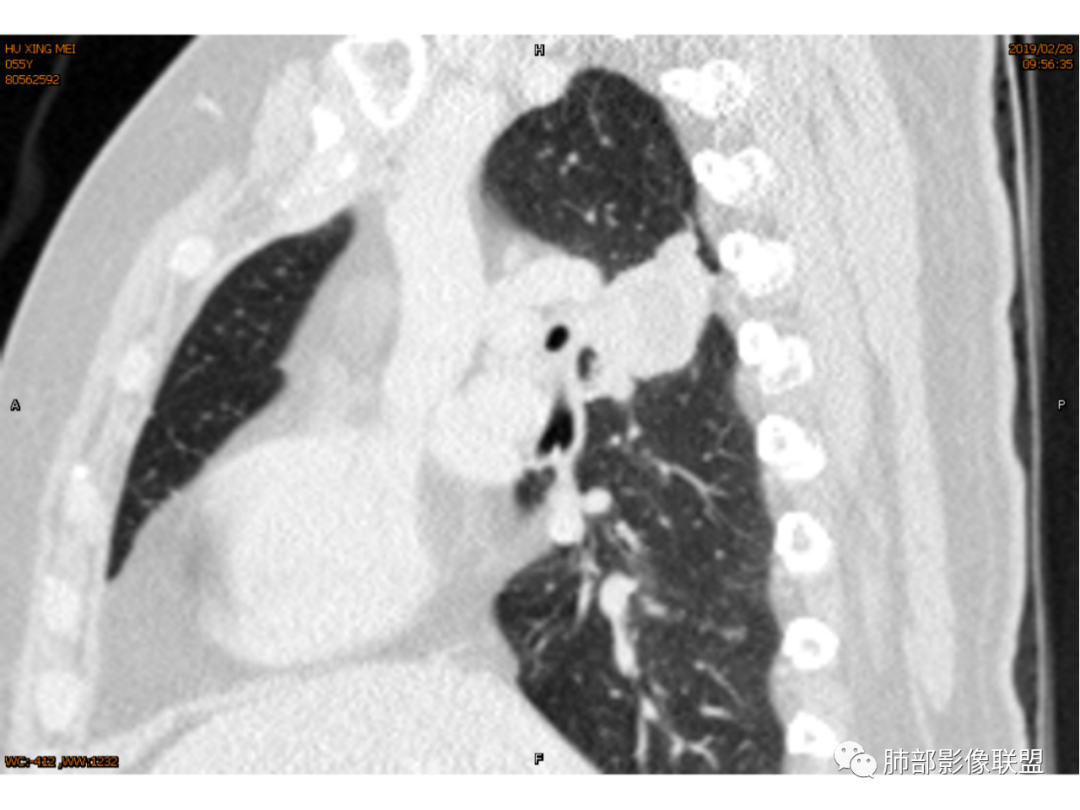

◆ 影像资料:

傅昌瑜:女性,咳嗽咳痰痰中带血1月。血常规、肿瘤标记物正常。CT:右上叶后段类圆形结节,内侧紧贴纵隔,前与右主支气管后壁分界不清。外后部分边缘平直收缩、矢状位可见U型凹陷、桃尖征,周围见边缘模糊的GGO,软毛刺。右上叶后段支气管似乎变狭窄。增强呈薄壁环形强化,内部强化不明显,强化时边缘似见有多个小结节与主病灶融合(芋艿子?)。远端见细小结节。整体考虑炎性病变,结核可能性大,注意鉴别腺癌。

右肺上叶肿块,靠近脊柱,类圆形,部分层面周围有晕,平直、凹陷、膨隆均有,水平位未见明显分叶,失状位重建有棘突/毛刺?局部叶间胸膜增厚,无明显牵拉僵硬,支气管通畅;中心无明显强化,周围环形强化影。临床:女性,亚急性病程,咳血。考虑:倾向良性,结核?

1.女性,咳嗽咳痰痰中带血1月。血常规、肿瘤标记物正常。             2.CT示右肺上叶不规则肿块,边缘以平直收缩为主,可见U型凹陷及桃尖征,周围见边缘模糊的GGO,软毛刺,从形态学的角度病灶更支持炎性改变; 3.增强呈薄壁环形强化,壁光整、清楚,也支持炎性改变;病灶内部平扫CT值密度比较高,约40HU,明显高于水的密度,而且未见强化,提示病灶的坏死可能为凝固性坏死;    4.从上面的分析,病变更符合炎性,患者白细胞不高,治疗后没有好转,不支持普通细菌的感染;影像病灶较局限,边界较清楚,病灶慢性炎症或肉芽肿,形态机发病部位更符合继发性肺结核。患者非易感人群,病灶孤立,尽管有液化,也很难第一时间考虑真菌,尤其是曲霉菌感染。什么是炎性肉芽肿?炎性肉芽肿的常见疾病谱系有哪些?那什么是凝固性坏死和干酪样坏死?跟一般的液化性坏死有什么区别?接下来我们逐一学习一下。